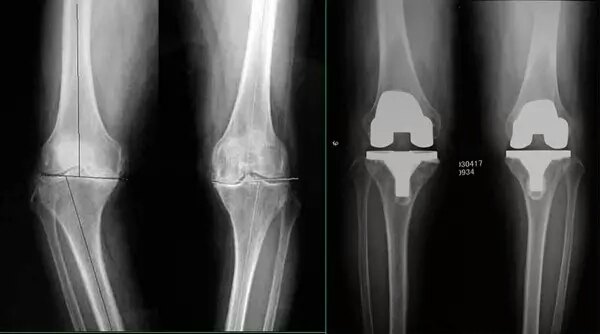

双膝骨性关节炎,屈曲内翻畸形.(膝关节表面置换术) - 好大夫在线

双膝骨性关节炎一期膝关节表面置换 [病例帖]